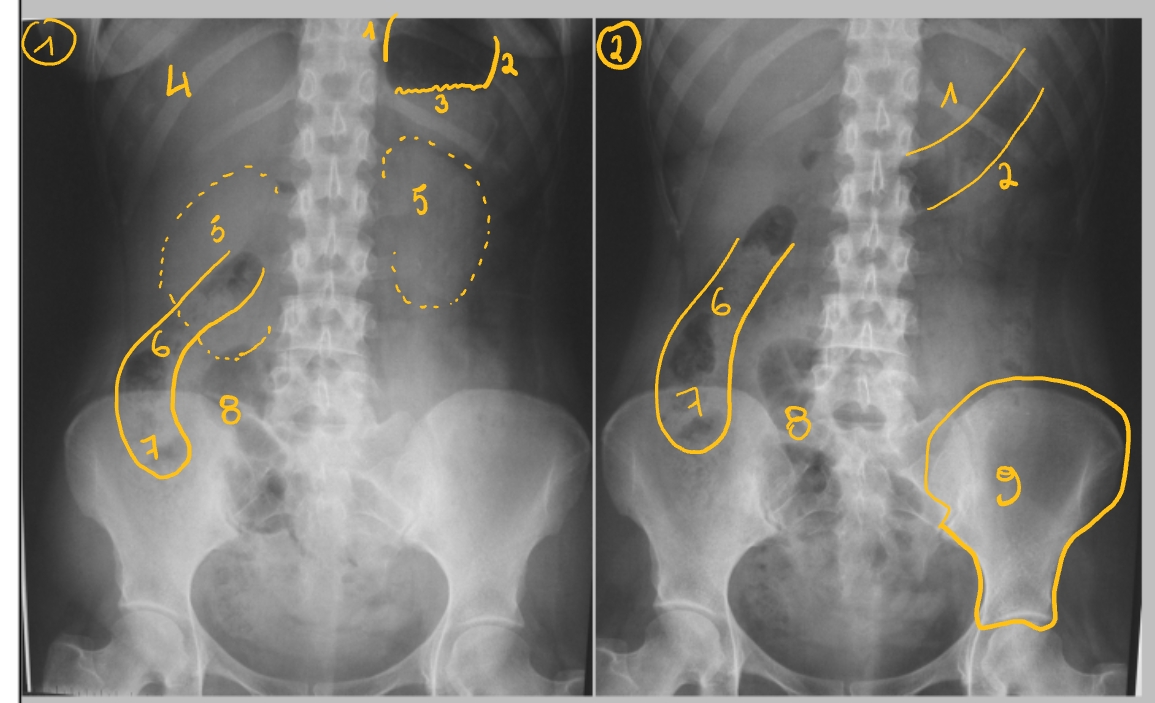

maag

duodenum, pars descendens

jejunum

ileum

laatste ileale lis

caecum

colon ascendens

→ A: haustra’s (lopen niet door)

colon transversum

colon descendens

colon sigmoideum

(in rechter fossa)

→ gaat over in colon

→ tussen beide: klep van Bauhin

plicae circulares